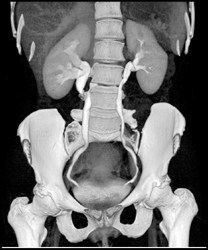

Penile Prosthesis Reservoir in Left Pelvis